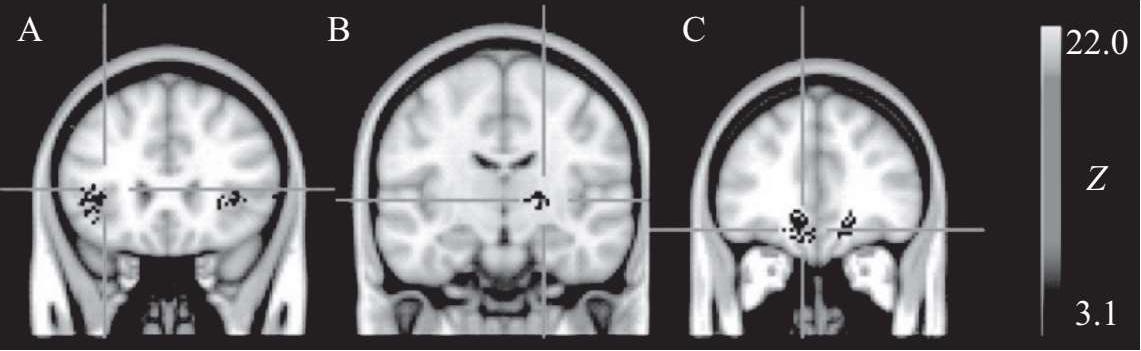

高强度运动可增加大脑奖励相关区域对低热量食物图像的神经反应(Crabtree D R,2014)

在肥胖防治领域,关键的研究方向之一是探索运动如何通过增加能量消耗来帮助减轻体重。然而,探讨运动是否能通过激励机制调节饮食行为和能量摄入的研究相对较少。近期的发现揭示了一些有趣的现象:例如,急性运动后,肥胖青少年的能量摄入和对食物相关信息的神经反应都有所下降,这一现象在非肥胖受试者中则未观察到。这意味着,尽管肥胖者运动后的总能量摄入未显著降低,但由于运动导致的能量消耗,能量平衡可能发生了变化。运动不仅可能增加饱腹感,还可能抑制由于享乐驱动的饮食行为。此外,运动锻炼对肥胖青少年体内与食欲相关的激素水平,如胰岛素、瘦素和生长激素释放肽等,都有显著影响。这些激素可能通过直接或间接作用于大脑的奖励系统(特别是VTA-NAc-DA神经元)来调节饮食行为和进食后的奖励感受。